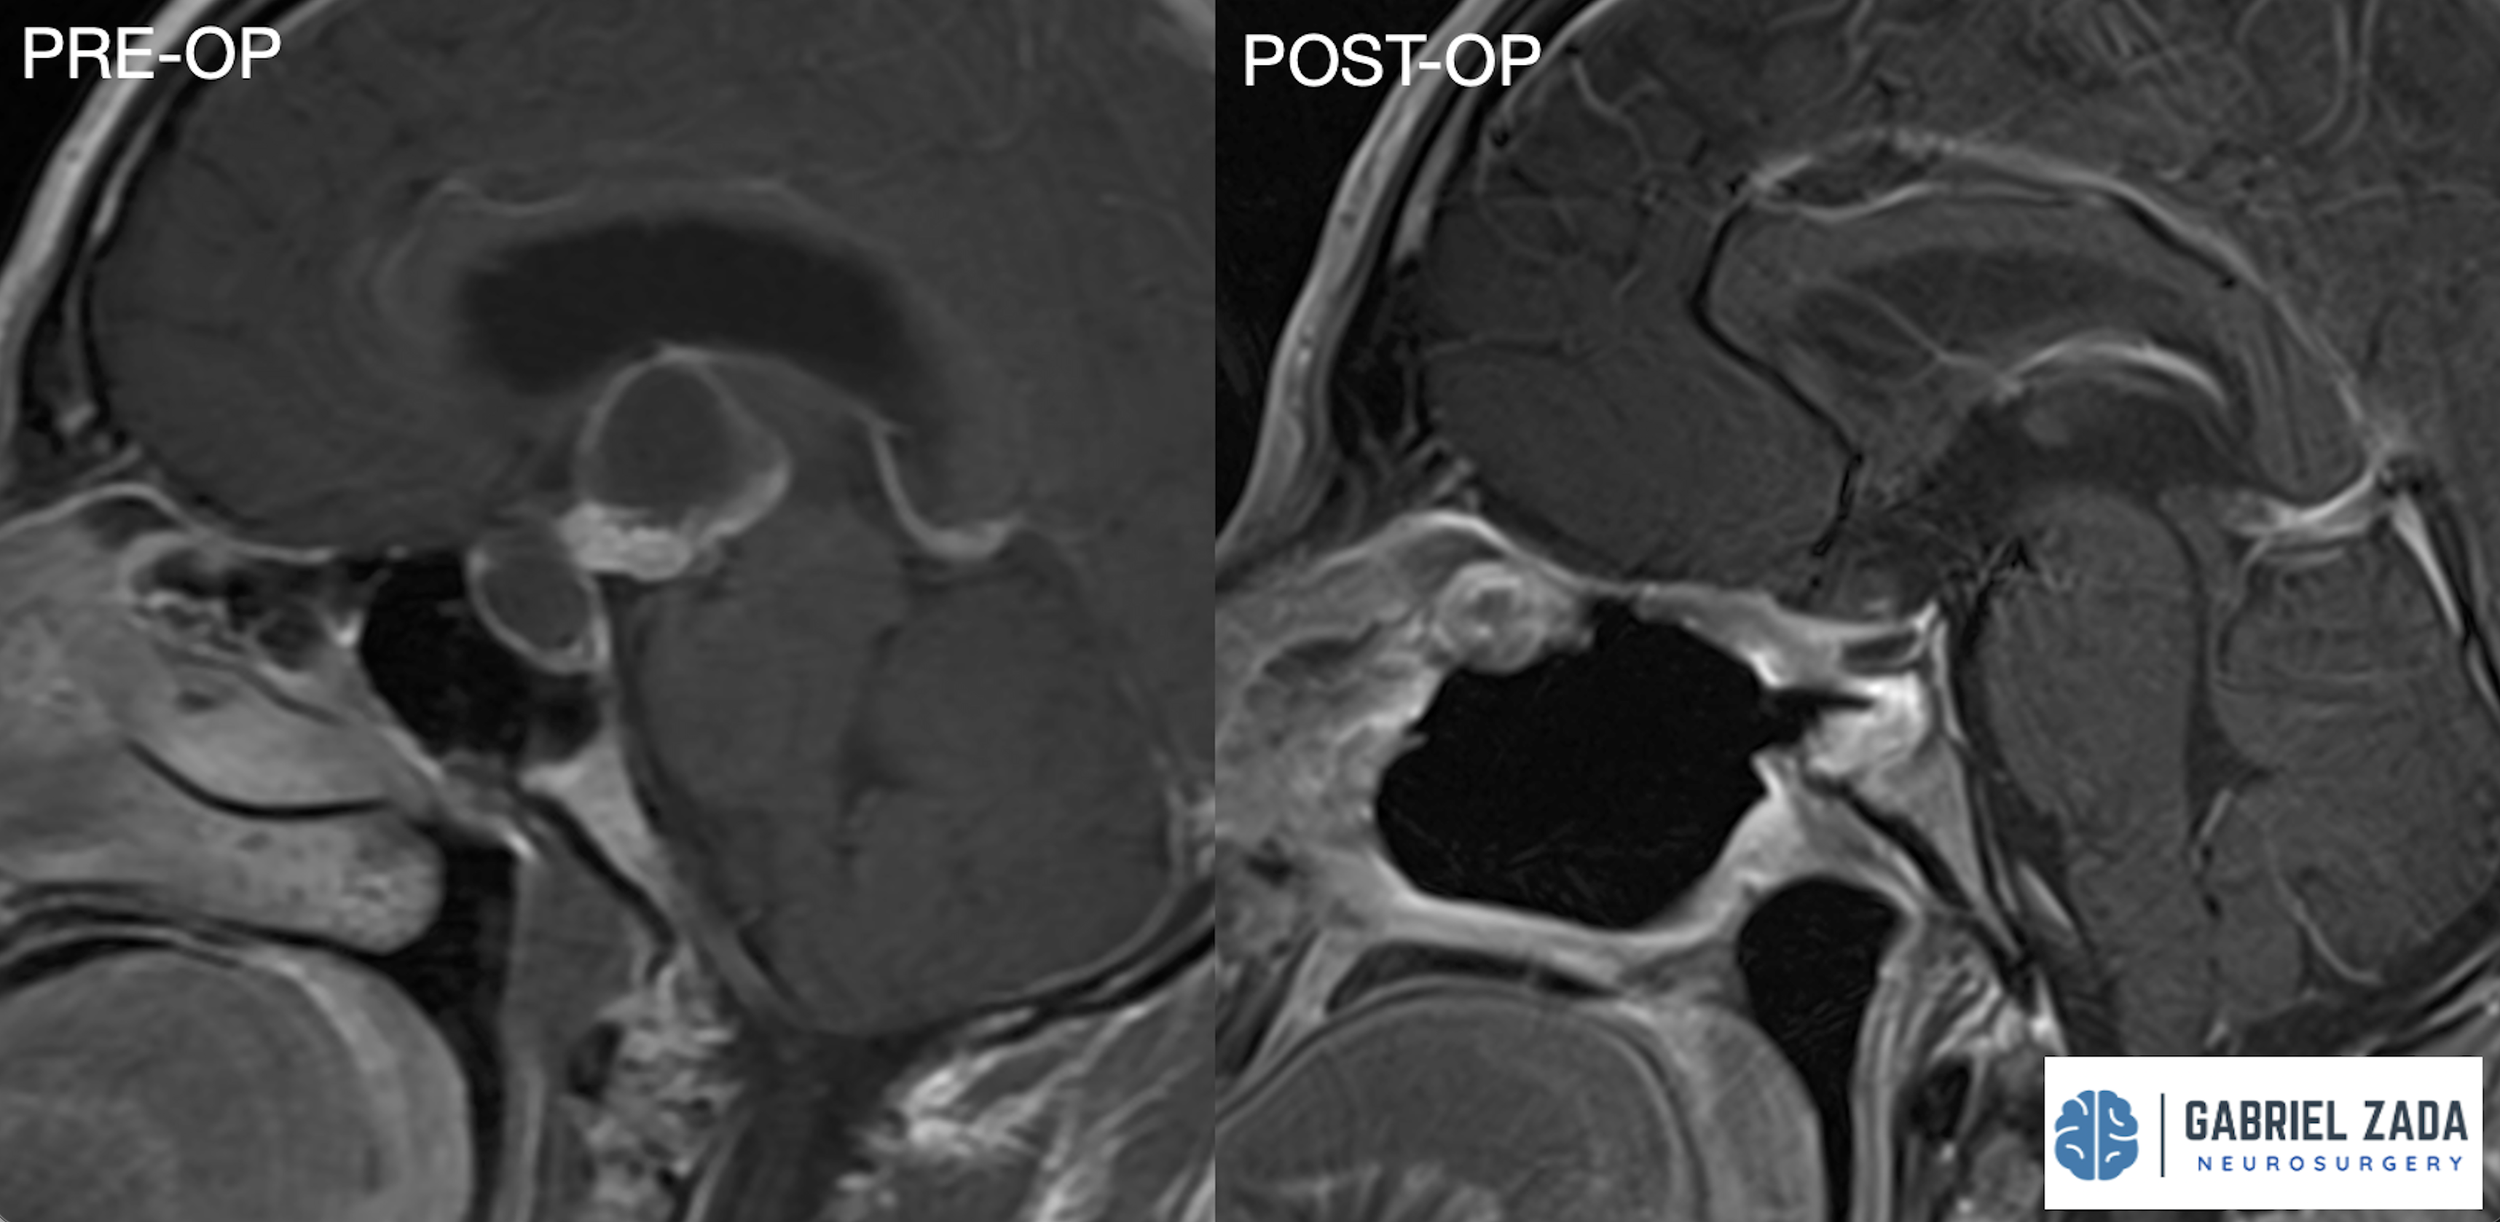

Explore this comprehensive gallery featuring pre‑ and post‑operative imaging of patients with skull‑base tumors treated by Gabriel Zada, MD, MS, FAANS, FACS. These cases highlight Dr. Zada’s expertise in advanced neurosurgical techniques and outcomes.

*Representative cases shown for educational purposes. All images de-identified. Individual results vary.